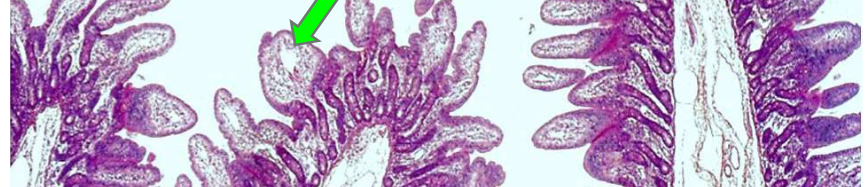

Q

What kind of cell is this in the nervous system? What is their puropse?

A

Ependymal Cell

They create the cerebral spinal fluid and form the Coriod Plexus